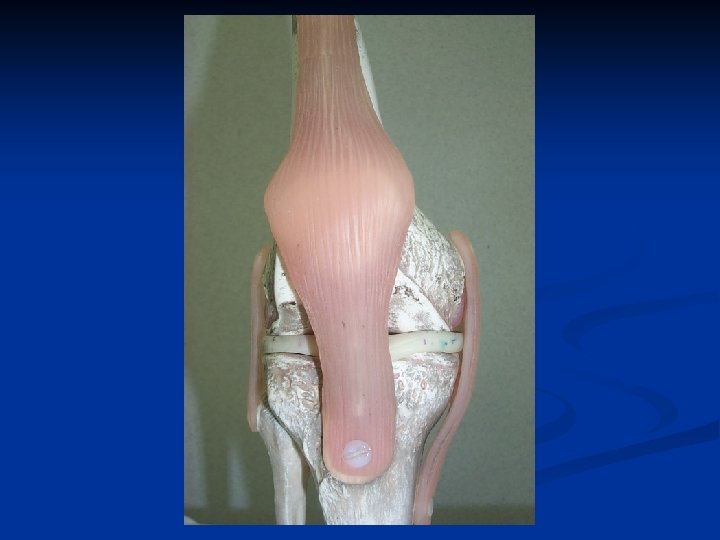

LIGAMENTOPLASTIE Greffe tendineuse prélevée au dépend du tendon rotulien, DIDT, fascia lata. n A ciel ouvert ou sous arthroscopie. n Permet une rééducation rapide. n Reprise de l’activité sportive au bout de six mois. n

PRELEVEMENT DU TENDON ROTULIEN